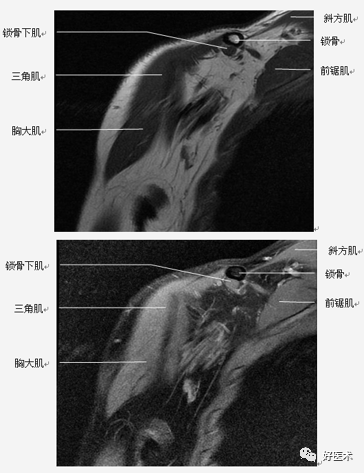

肩关节非固有肌群:斜方肌、背阔肌、肩胛提肌、菱形肌、前锯肌、胸大肌、胸小肌、锁骨下肌。